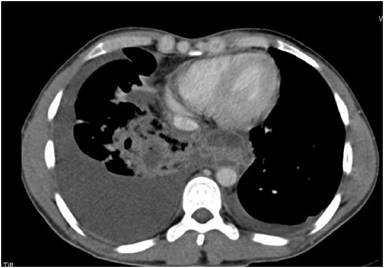

A thirty fouryears old male with history of alcohol related acute pancreatitis was admitted with right sided chest pain and breathing difficulty. Chest X-ray revealed moderate right pleural effusion, pleural fluid amylase was grossly elevated measuring 35, 590 U/L.CT demonstrated pancreatic ductal disruption in body of pancreas with a tract through esophageal hiatus and small mediastinal pseudocyst. There was also central peribronchovascular consolidation in the lower lobe of right lung with hypodense collections in the lung parenchyma and was judged to be pancreatico-bronchial fistula through these intraparenchymal collections due to the patient developing characteristic expectoration of copious amount of rusty brown coloured sputum during his hospital stay (Figure 1).

Figure 1. Chest CT demonstrates small posterior mediastinal collections along with lung parenchymal consolidations and small collections due to pancreatico-pleura-bronchial fistula. |